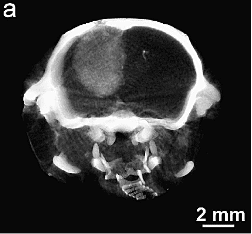

Curing brain cancer in mice with Gold NPs + RT

Brain tumors could be imaged at high resolution (Fig. 3) and combined with RT produced 50% long-term survival (Fig. 4).

Read the article: “Gold nanoparticle imaging and radiotherapy of brain tumors in mice” https://doi.org/10.2217/nnm.12.165